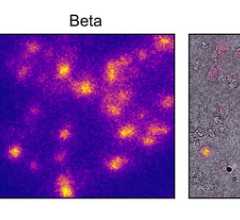

March 22, 2023 — A novel imaging modality that can visualize the distribution of medical radiopharmaceuticals with very ...

March 20, 2023 — Researchers from UNSW Sydney have developed an algorithm which produces high-resolution modeled images ...